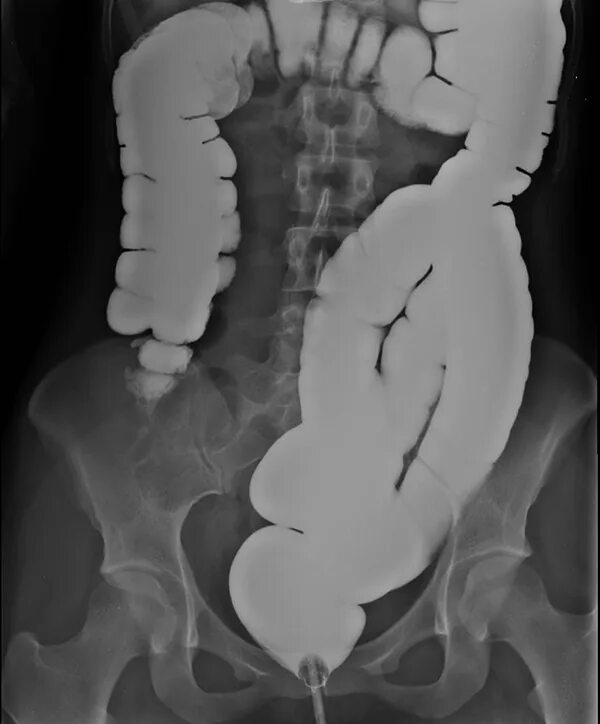

Кишечник после ирригоскопии